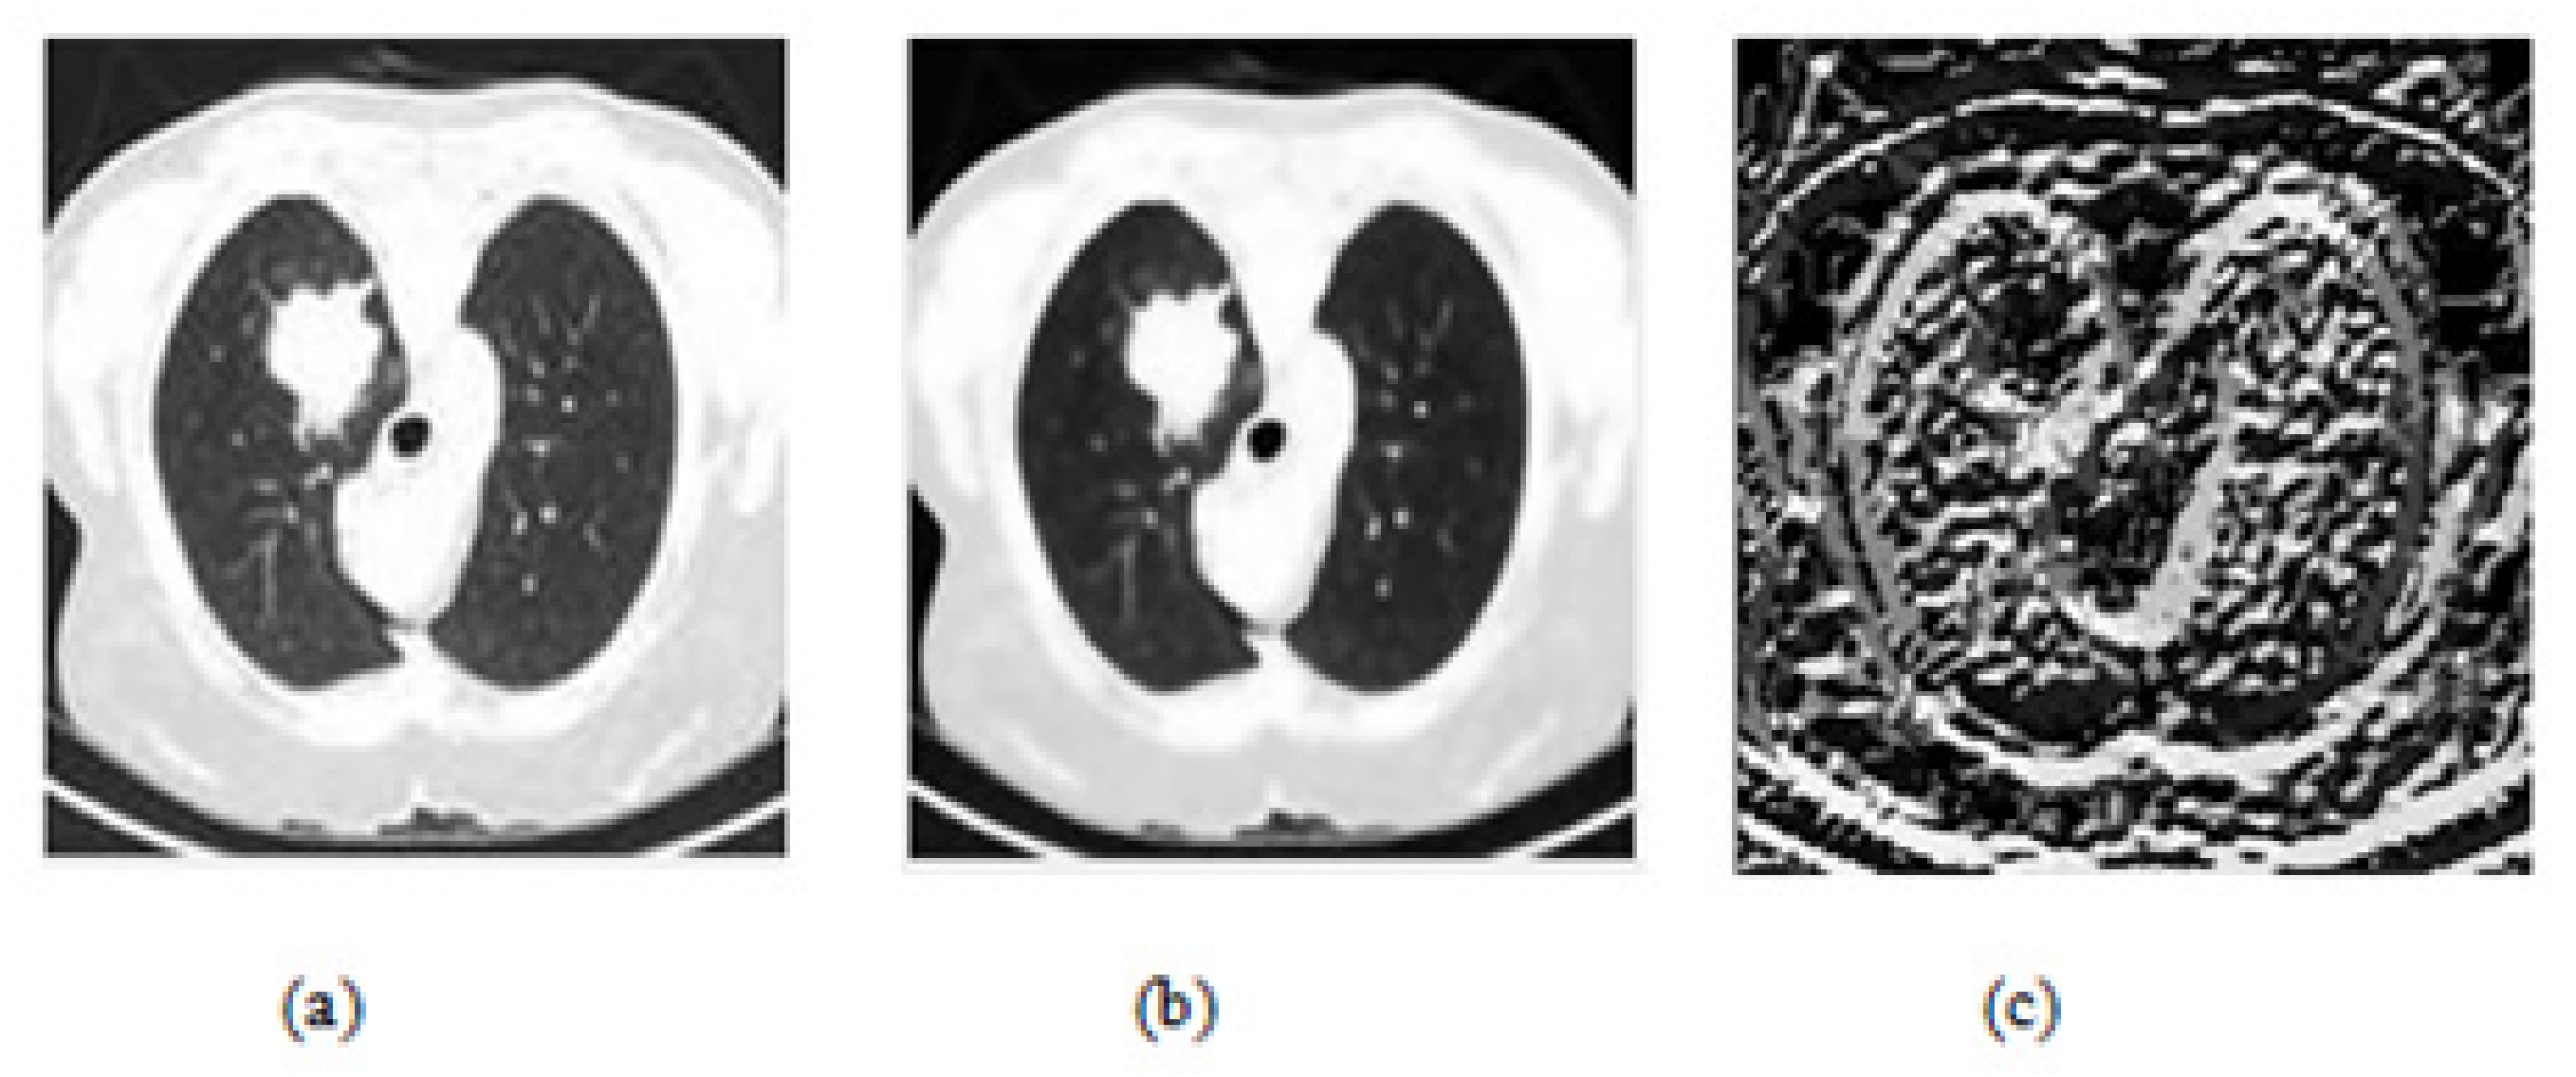

2.2. Preprocessing

4.1. Pre-Processing Result